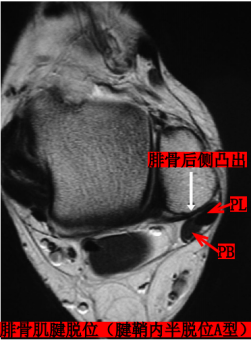

Raikin等学者提出将腓骨沟内腱鞘内半脱位不伴有腓骨上支持带损伤划为腓骨脱位的亚系。这些腱鞘内半脱位共有两型:

A型:腓骨肌腱无撕裂,肌腱暂时换位;

B型:腓骨短肌存在纵向撕裂,腓骨长肌腱自撕裂处半脱位。

MRI:能更清楚地显示软组织损伤情况,如支持带撕裂和腓骨肌腱半脱位。对于指导临床治疗及后期随访观察疗效具有重要参考价值。